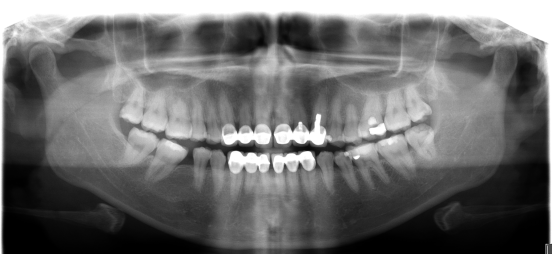

拍摄旧义齿口腔ct全景

考虑到董女士牙齿的特殊性和出现的问题,熊少军医生专门为她量身订做了一套麦芽数字化全瓷修复方案。